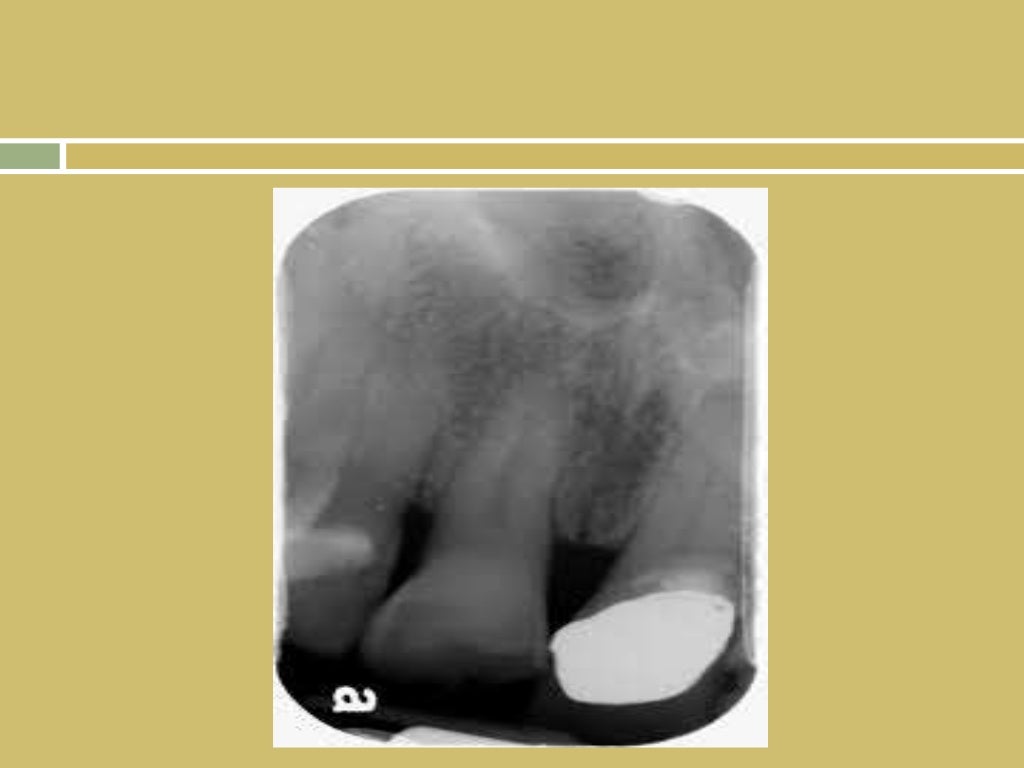

normal radiographic anatomy of oral cavity

Normal Radiographic Anatomy Maxillary Lateral Area Semantic Scholar Radiographic Oral Anatomy the mandible is the single midline bone of the lower jaw. the oral cavity is a challenging area for radiological diagnosis. The oral cavity is bounded anteriorly by the lips, inferiorly by the tongue and floor of the mouth,. Oral cavity is broadly divided into a central larger portion called “oral cavity proper” and an outer. Interpretation of. Radiographic Oral Anatomy.